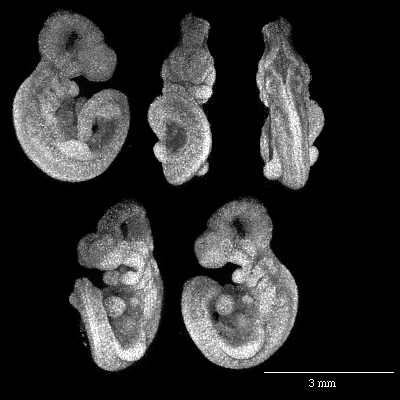

Magnetic resonance imaging of a normal day 10.5 mouse embryo.

MRI of a mouse embryo